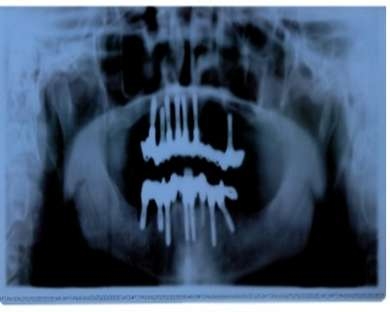

Die Implantologie nimmt einen immer bedeutenderen Stellenwert in der Zahnheilkunde ein. Implantate und entsprechende Knochenaufbaumaßnahmen können heute bei fast allen Patienten die Voraussetzungen für die Eingliederung eines festsitzenden Zahnersatzes schaffen. Letztendlich sind es nur noch Kostenfaktoren, die in vielen Fällen die Ursache für die Eingliederung einer Brücke oder Prothese anstelle der Inkorperation eines oder mehrerer Implantate darstellen. Während die Notwendigkeit der präoperativen Vorbereitung auch für die Patienten meistens gut verständlich ist, gelingt es nicht immer eine ausreichende Motivation für regelmäßige Kontrolluntersuchungen, nach dem Eingriff und Versorgung der Implantate mit Zahnersatz, zu erreichen. Gerade die Nachsorge ist aber ausgesprochen wichtig. Regelmäßige Termine zur Professionellen Zahnreinigung in ca. 3-monatigen Abständen sind sehr wichtig um z. B. die Entstehung einer Periimplantitis zu vermeiden. Die Periimplantitis ist eine Knochenentzündung, die sich um ein Implantat herum bilden kann. Sie geht einher mit einem Knochenverlust, der Ausbildung von Taschen und kann letztendlich nach umfangreichem Knochenverlust zu einer Lockerung des Implantates und damit zum Implantatverlust führen. Neben Planungsproblemen (z. B. falsches Kronen-Wurzel-Verhältnis) ist vor allem eine unzureichende Hygiene nach der prothetischen Versorgung der Implantate die häufigste Ursache für eine Periimplantitis.

Wird die Diagnose einer Periimplantitis gestellt, sollte unbedingt der Spezialist für die Implantologie (der Facharzt für Mund-, Kiefer- und Gesichtschirurgie) aufgesucht werden, um eine rasche Behandlung dieser entzündlichen Veränderungen einzuleiten. Neben der genauen Definition des vorhandenen Keimspektrums und einer antibiotischen Abdeckung ist vor allen Dingen die Beseitigung des das Implantat umgebenden entzündlichen Gewebes wichtig. Dieses kann idealer Weise mit einem Laser erfolgen. Der um das Implantat entstandene Knochendefekt muss dann durch entsprechende Aufbaumaßnahmen aufgefüllt werden.

Hierfür stehen unterschiedliche Materialien zur Verfügung. Grob kann man unterscheiden zwischen synthetischem Material oder Knochensubstanz. Von der Nutzung von tierischem Knochen – auch in aufbereiteter Form – geht man immer weiter ab, da trotz einer sehr hohen Virussicherheit letztendlich doch immer die Angst bleibt, dass durch tierischen Knochen Viren übertragen werden könnten. Besser ist dann die Nutzung von körpereigenem Knochen, der z. B. am Beckenkamm, an der Kniescheibe, dem Unterschenkelknochen oder auch in der Mundhöhle gewonnen werden kann. Dieser Knochen wird dann aufgearbeitet und in den Knochendefekt eingebracht. Wichtig ist es, dass dieser Knochen im Defekt stabilisiert wird und keine Beweglichkeit des Transplantates entsteht, da beweglicher Knochen relativ rasch resorbiert wird, was zum Ausgangsproblem zurückführt. Zumindest bei der Nutzung von synthetischem Knochen ist die Abdeckung mit einer resorbierbaren Membran äußerst wichtig. Auf diese Weise gelingt es in einem hohen Prozentsatz der Fälle, die um das Implantat herum befindliche Entzündung zu beherrschen und das Implantat zu erhalten. Gelingt es nicht den Knochendefekt zu augmentieren, weil z. B. der Knochen aus unterschiedlichen Ursachen immer wieder verloren geht, ist es sehr wichtig zumindest die Reinigungsfähigkeit zu erhalten.